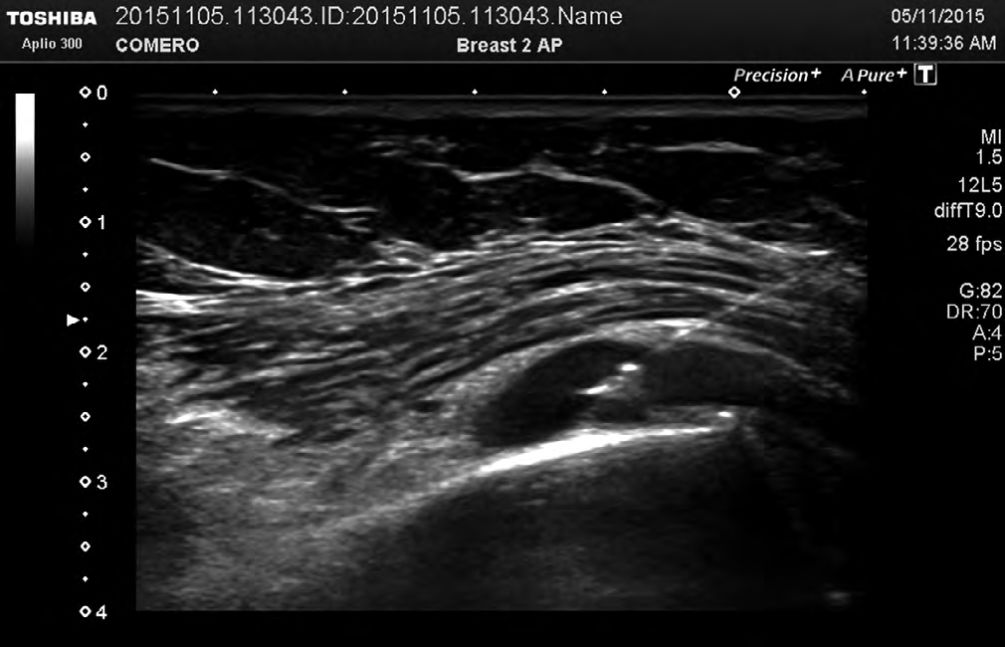

Foto 4 y 5

Aspiración de bursitis SASD se observa punta de la aguja dentro de la bursa, obteniéndose 10cc de líquido. Una vez aspirado se administraron los fármacos

Cuando la bursa SASD no está distendida, es un espacio virtual.

Es así que se debe introducir la aguja muy despacio, e ir inyectando de a pequeñas cantidades hasta alcanzar esta “línea” formada por la interfase deltoides/supraespinoso. Cuando efectivamente se está en el lugar indicado, se forma una lámina líquida, que va desplegando esta interfase a medida que se inyectan los fármacos. Dada la precisión que requiere esta maniobra, pensamos que una maniobra a ciegas en la inmensa mayoría de las veces infiltrará o bien al músculo deltoides, o al tendón del supraespinoso.